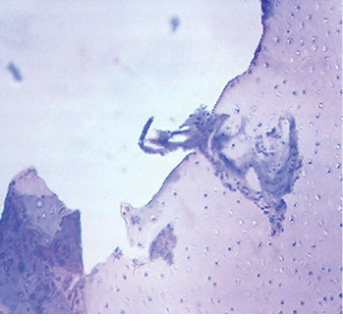

Через 1 мес от начала эксперимента

Контрольный сустав (правый): движения в суставе ограничены, глубина кратера «минус-ткань» сформированного очагового дефекта составляет 3/4 толщины, края не сглажены, чётко прослеживается граница между новообразованной тканью и окружающей хрящевой тканью. Микроскопически обнаружены признаки неполной репаративной регенерации хрящевой и костной ткани. Новообразованный гиалиновоподобный суставной хрящ несёт в себе свойства незрелого.

1-я экспериментальная группа (левый сустав): движения в суставе ограничены, глубина кратера «минус-ткань» сформированного очагового дефекта составляет 3/4 толщины, края не сглажены, чётко прослеживается граница между новообразованной тканью и окружающей хрящевой тканью. Микроскопически полость остеохондрального дефекта на 1/3 заполнена фиброретикулярной тканью с наличием новообразованных сосудов. Отмечается пролиферация фибробластов. Определяются единичные хондрогенные островки.

2-я экспериментальная группа (левый сустав): определяются ограничения движений в суставе, «минус-ткань», составляющая 1/2 толщины сформированного дефекта с ровными гладкими краями, граница между новообразованной тканью и сохранённым гиалиновым суставным хрящом прослеживается чётко, поскольку новообразованная ткань резко полнокровна. Микроскопически в полости дефекта формируется органотипический соединительнотканный регенерат. В периостальной зоне регенерата имеются хондрогенные островки, имеющие то же строение, что и в 1-й экспериментальной группе, но больше по размерам, в количестве 5 в поле зрения микроскопа.

3-я экспериментальная группа (левый сустав): движения в суставе ограничены, определяется «минус-ткань», составляющая 1/3 толщины сформированного дефекта, с ровными гладкими краями, граница между новообразованной тканью и сохранённым хрящом прослеживается чётко, новообразованная ткань резко полнокровна. Микроскопически органический регенерат из фиброзной ткани полностью заполняет полость дефекта и плотно сращён с его стенками, коллагеновые волокна формируют плотные пучки. Отмечается усиленная пролиферация фибробластов. В фиброретикулярной ткани определяется большое число хондрогенных островков (>10 в поле зрения).

За 1 мес во всех группах произошли макро- и микроскопические изменения, представленные в табл. 1.